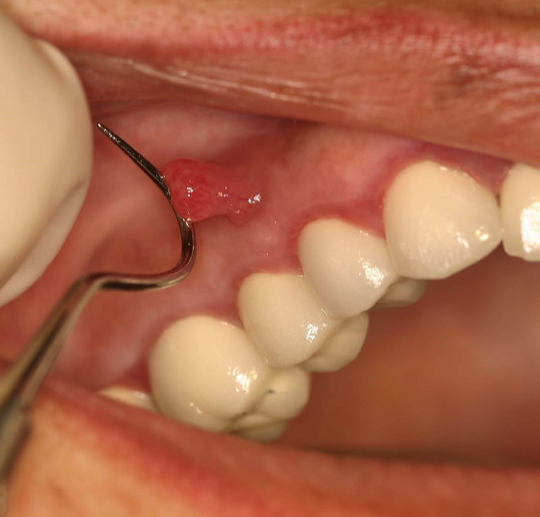

3 clinical signs of parulis

dome-shaped yellow-pink papule

may/may not exhibit active suppuration (pus formation)

parulis is usually located where

on gingiva facial to non-vital tooth

what is this

chronic hyperplastic pulpitis: hyperplastic granulation tissue extrudes from pulp chamber

chronic hyperplastic pulpitis usually happens in which age

children + young adults w/ large pulp exposures

2 tx options for chronic hyperplastic pulpitis

endo

ext